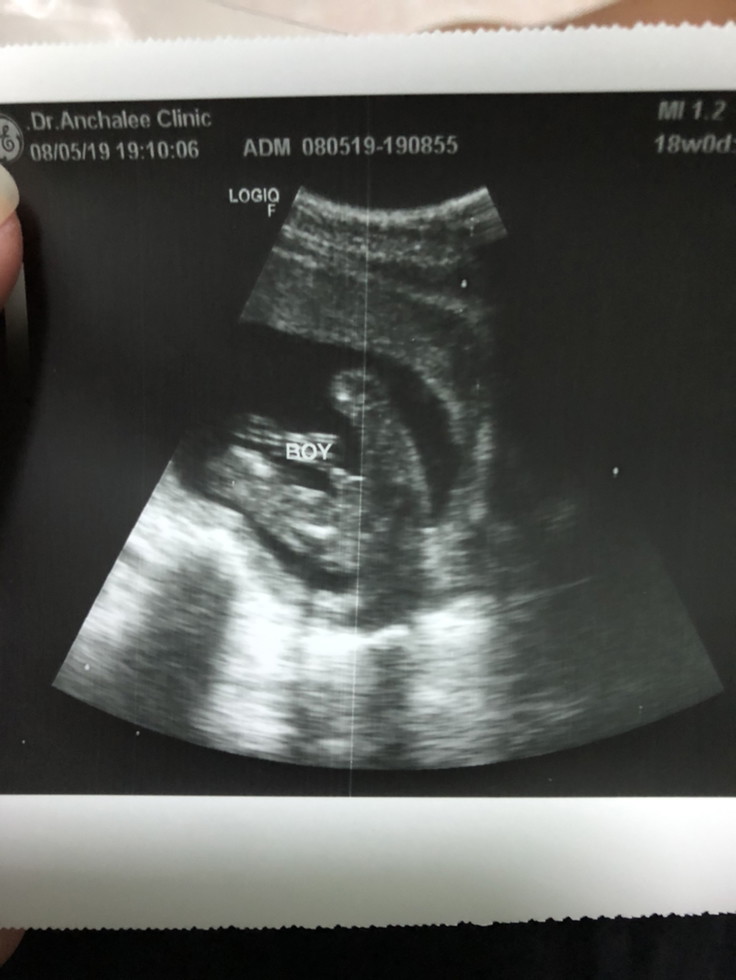

หมอบอกชาย18w

18 week จ้า

18 weeks 🥰